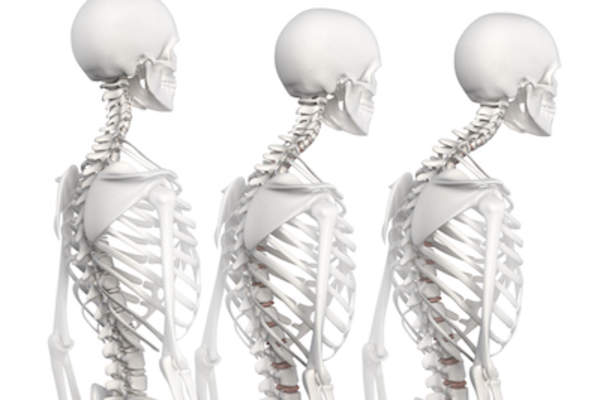

后凸